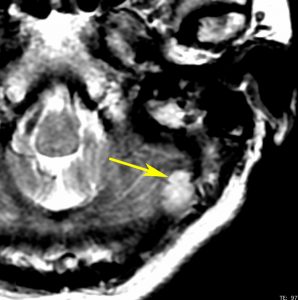

40代男性の大脳鎌テント接合部の硬膜に発生したグレード3です。激しい出血のために腫瘍摘出を部分摘出で中断せざるを得なかった例です。

この例でも,硬膜発生腫瘍ということは手術前の画像診断で解ってはいたのですが,髄膜腫と異なり不整な形をしてのう胞があり,一部は腫瘍壊死でした。